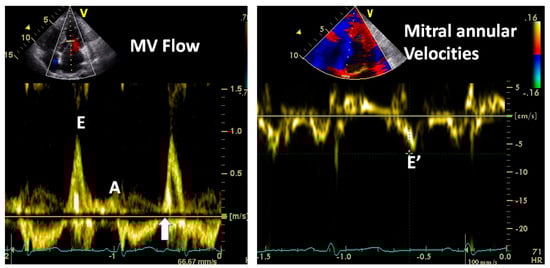

3.2.1. Transmitral Flow

| Factors affecting E wave amplitude: |

| Impaired LV relaxation reduces E wave amplitude |

| High LA pressure increases its amplitude |

| Exaggerated LV recoil increases its amplitude |

| Factors affecting mitral A wave amplitude: |

| Left atrial contractile function: reduced in atrial cardiomyopathy, post cardioversion |

| Atrial preload: larger LA volume at the time of systole boosts the atrial transport function |

| Atrial afterload: Higher LVEDP or pre-A pressure will reduce atrial contribution |